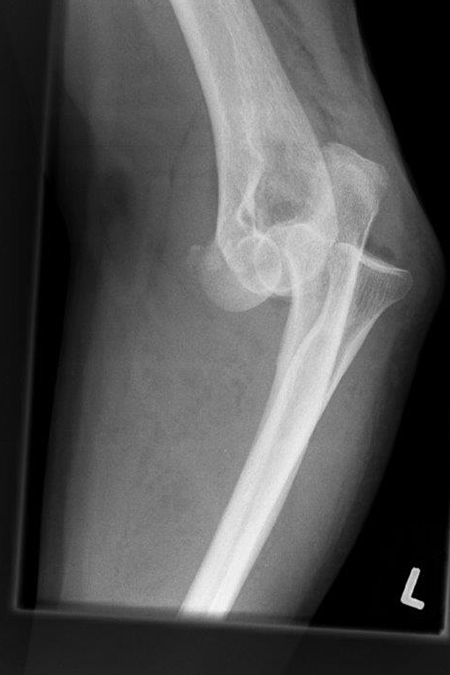

Bei einer Verrenkung (Luxation) des Ellenbogengelenkes kann es zu schweren Verletzungen des Knochens und der Weichteile kommen. Typisch ist der Sturz auf den leicht gebeugten außengedrehten Arm der zu einer Verrenkung (Luxation) des Ellenbogengelenks führt. Dabei springt in den meisten Fällen das Speichenköpfchen über die Oberarmrolle hinweg nach hinten heraus und kann sogar an der Oberarmrolle zerbrechen (Typ Mason IV).

Je nach Ausmaß der Verrenkung reichen die Kapsel- und Bandeinrisse um das Gelenk bis zur Ellenseite herum und führen so zu einer Instabilität des Ellenbogengelenks. Die unkomplizierte Luxation, die schnell einer Einrenkung (Reposition) zugeführt wird, heilt in den meisten Fällen auch ohne Operation aus.

Zeigt die Stabilitätsprüfung des Gelenkes nach Reposition eine Instabilität oder liegen Frakturen vor, wird eine operative Rekonstruktion erforderlich.

Rechtshändiger Fotograf mit hoch instabiler Ellenbogenluxationsverletzung links. Operative Stabilisation mit Rekonstruktion der Bandstrukturen des Ellenbogengelenkes außen und innenseitig unter Einsatz einer Augmentationstechnik (Internal Bracing).

Ventrale Luxation Ellenbogen

Ellenbogengelenk herausgesprungen frontal

Ellenbogengelenk herausgesprungen seitlich